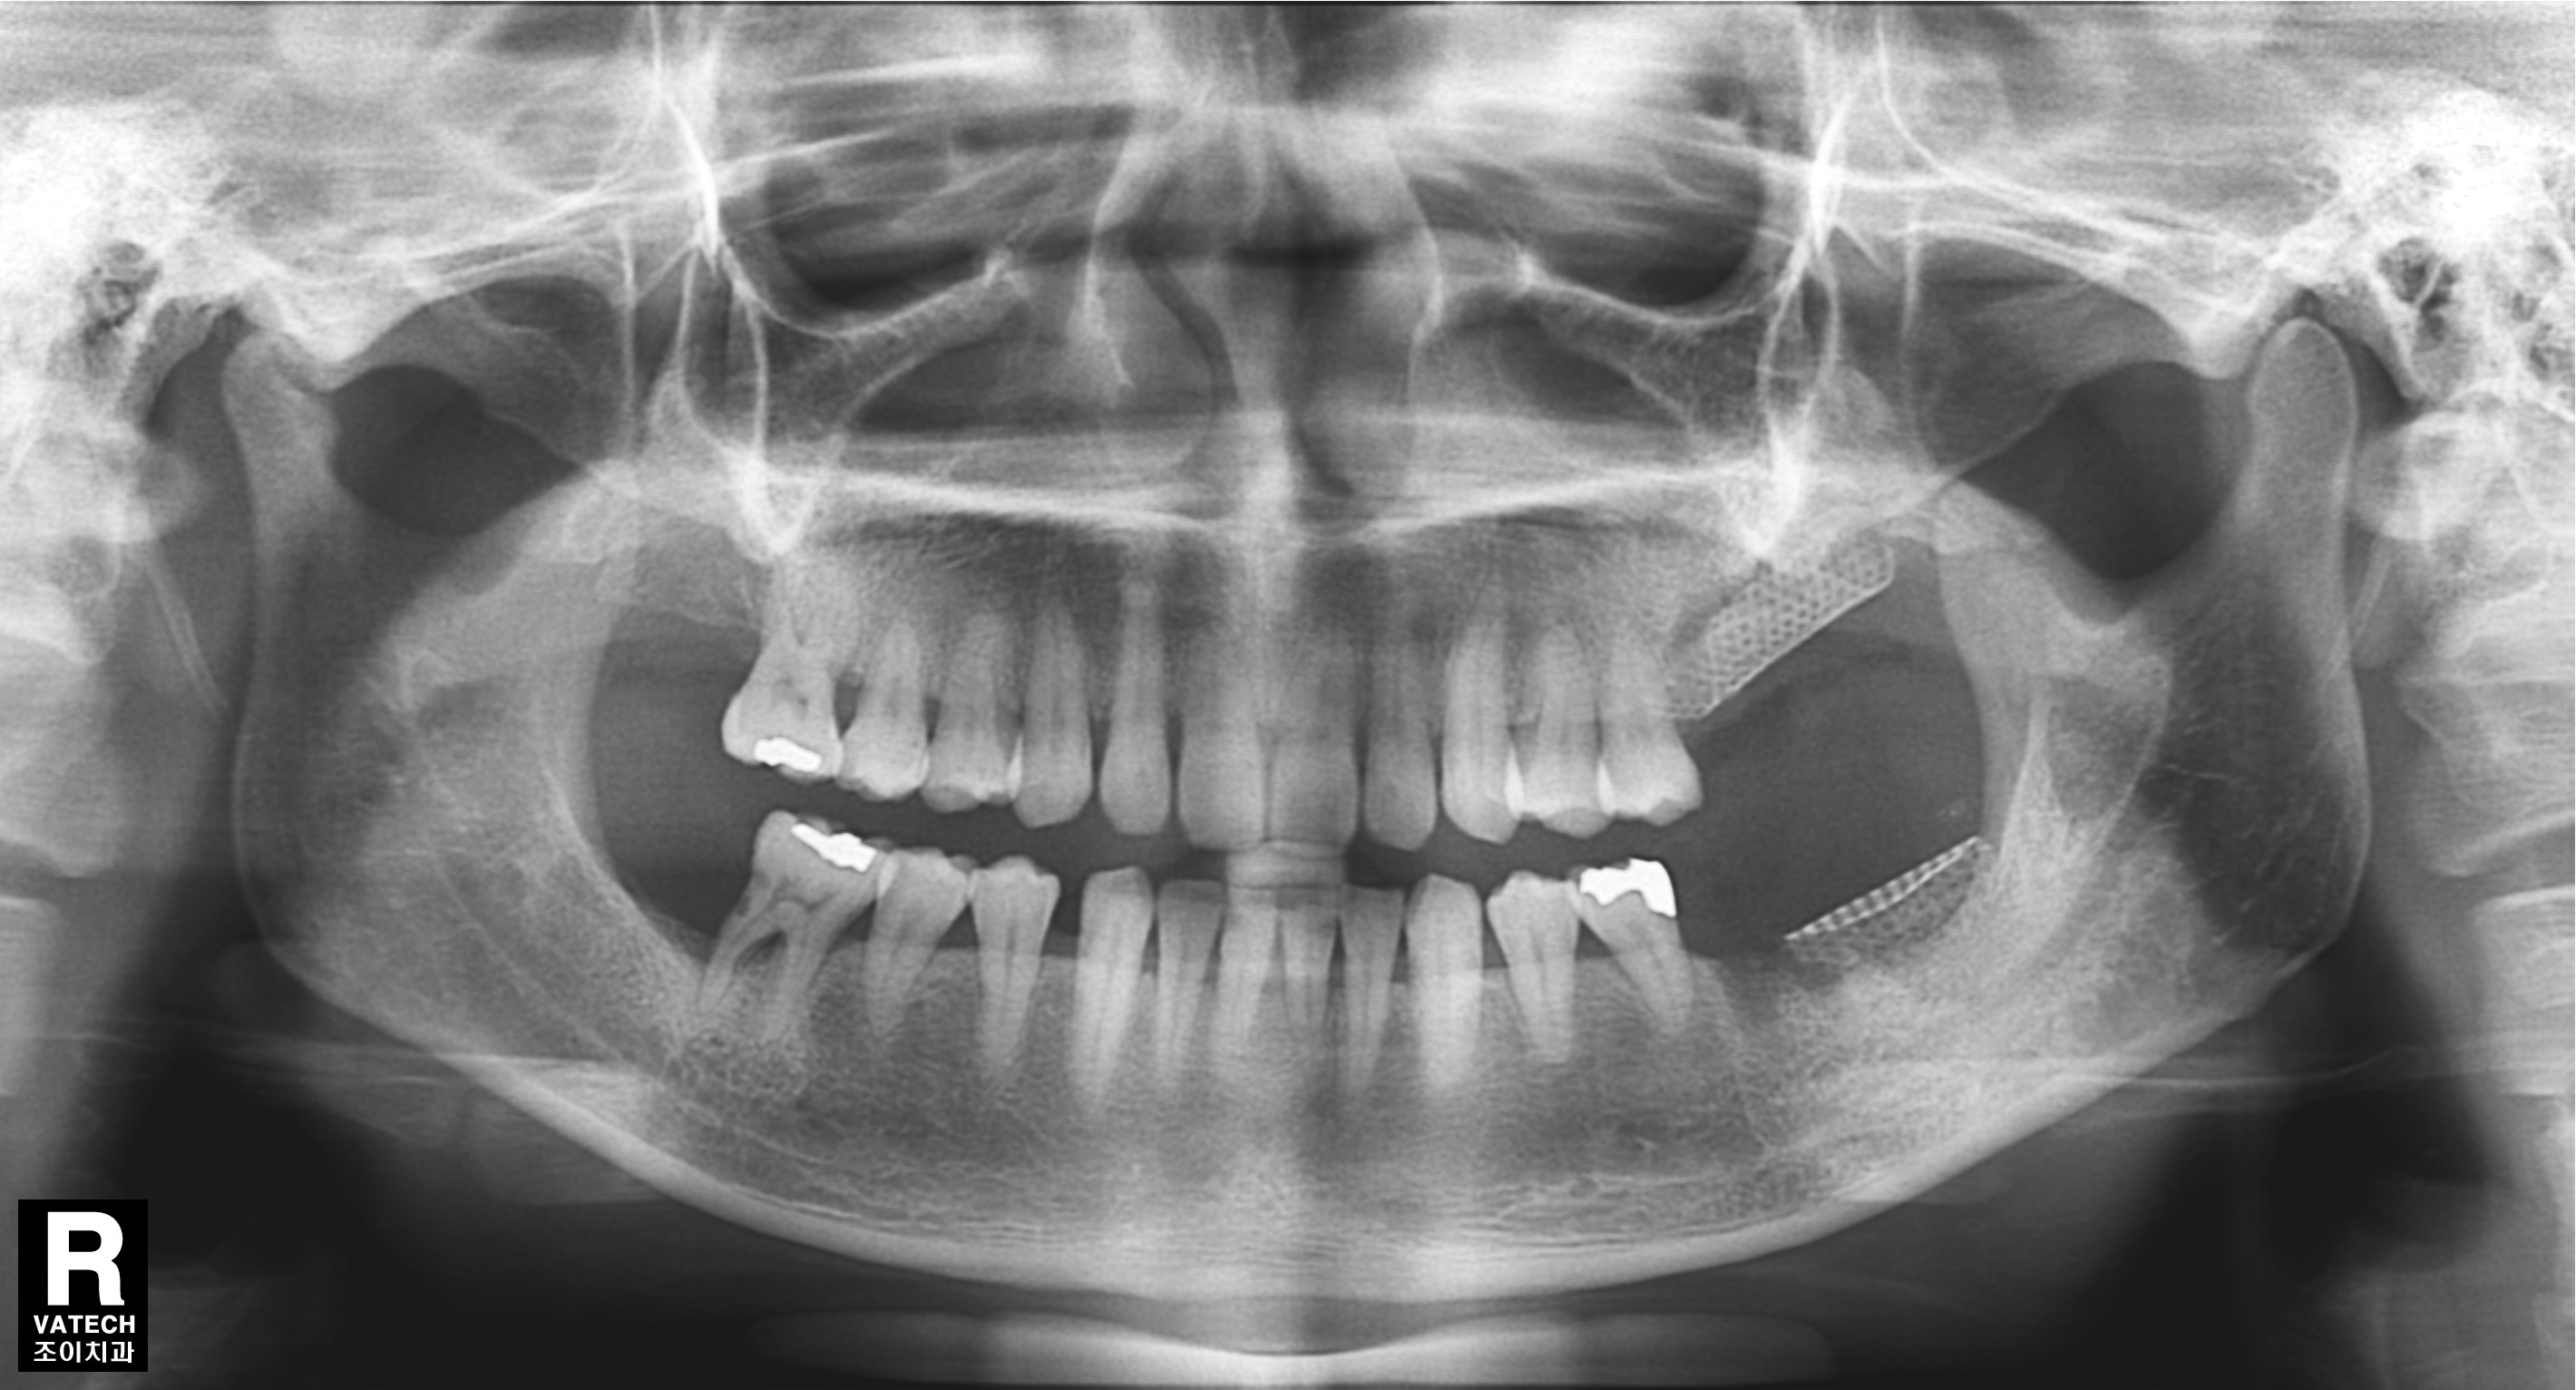

[임플란트] 제목 : 잇몸뼈가 심하게 녹은 환자에서의 임플란트

치주질환으로 치조골이 많이 녹아 내려간 경우 원하는 위치에 바로 임플란트를 심을 수 없는 경우가 많습니다.

또한 임플란트의 실패율도 높아집니다.

이 경우 골을 이식하는 것을 먼저 하고 수개월이 경과한 후에 다시 임플란트를 심어야 합니다.

그래야 원하는 위치에 임플란트를 심을 수 있고, 성공율을 높이며, 장기간 문제 없이 잘 유지할 수 있습니다.